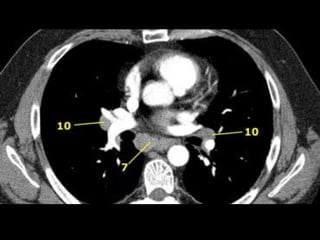

10. Hilar LNs

7. Subcarinal LNs

• Upper border: carina of the trachea.

• Lower border: bronchus intermedius on

the right and left lower lobe bronchus on

the left.